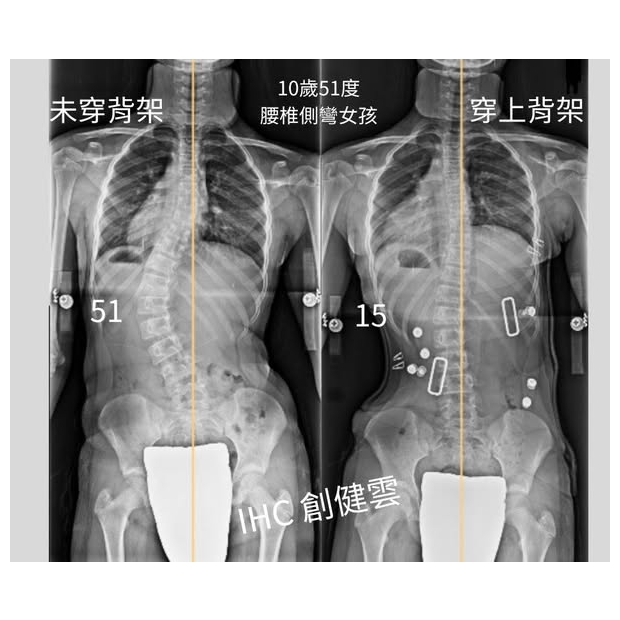

10歲脊椎側彎女孩,腰彎51度

10歲脊椎側彎女孩,腰彎51度 穿上背架後立即矯正效果優異